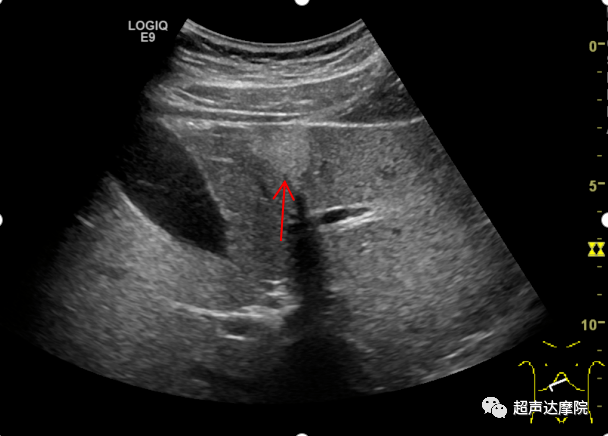

肝左内外叶的超声分界(肝圆韧带-门静脉左支矢状部-静脉韧带)